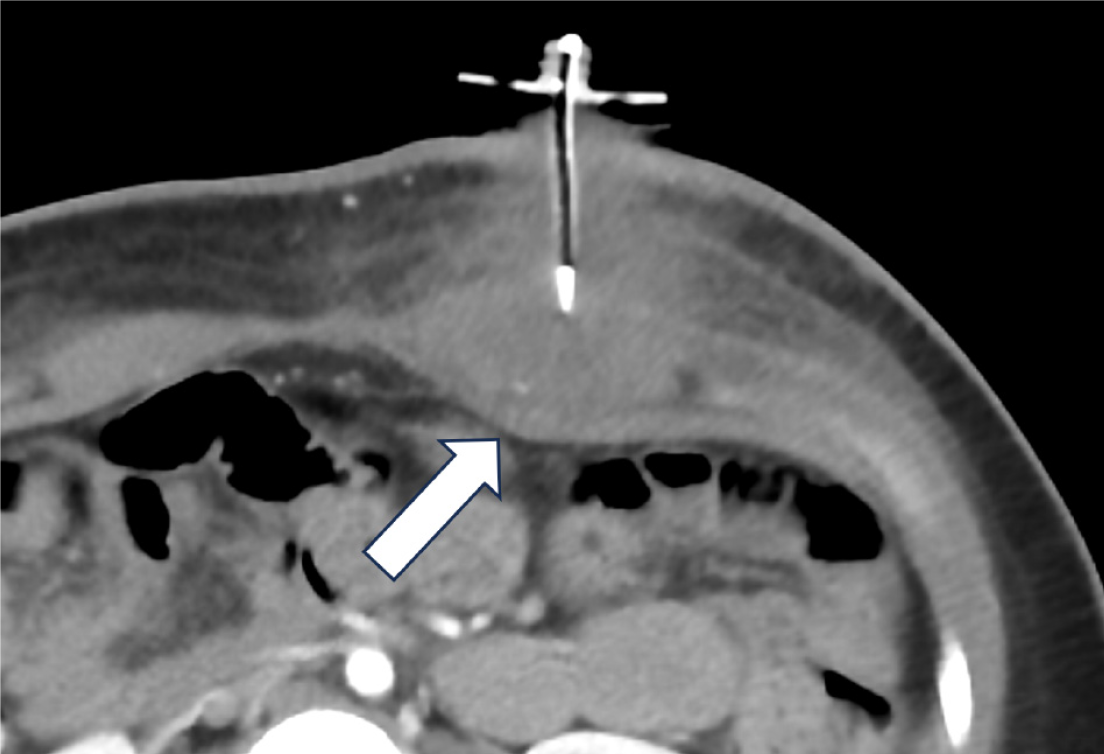

Figure 4 Intraperitoneal leak via the gastrostomy tube tract, 2 month old postoperative day 1 open gastrostomy tube placement.

A: Frontal abdominal radiograph with a large amount of pneumoperitoneum (black arrows); B: Frontal projection in a fluoroscopy gastrostomy tube (G-tube) study with a loculated intraperitoneal leak (outlined by white dotes). There is transit of contrast behind the G-tube ballon (star) into the peritoneal leak (arrow); C: G-tube was exchanged in interventional radiology, following which a lateral fluoroscopic image showed the narrowed distance (double arrow) between the disc and ballon with no trickling of contrast behind it.